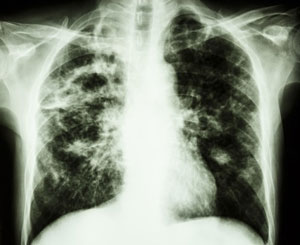

Samoistne włóknienie płuc jest przewlekłym, postępującym procesem zapalnym o nieznanej przyczynie, powodującym włóknienie tkanki płuc, a w efekcie spadek ich pojemności i trudności w wykonywaniu prostych codziennych czynności, takich jak chociażby chodzenie czy toaleta. Rokowanie w tej chorobie jest zawsze niepomyślne, a średni okres przeżycia krótszy niż w przypadku wielu nowotworów złośliwych, takich jak np. rak piersi, prostaty czy jelita. Zaledwie 25 proc. chorych przeżywa 5 lat od momenty rozpoznania. Na podstawie danych zebranych w państwach europejskich oraz Stanach Zjednoczonych szacuje się, że na samoistne włóknienie płuc zachorowuje rocznie ok. 5 osób na każde 100 tysięcy. W Polsce liczba ta szacowana jest na około 1 800 osób rocznie. Rzadkie występowanie choroby powoduje, że większość lekarzy nie rozpoznaje jej, co jest przyczyną błędów i opóźnień w diagnozie, stosowania nieprawidłowego leczenia i narażania chorego na działania niepożądane, a systemu ubezpieczeń na dodatkowe koszty.